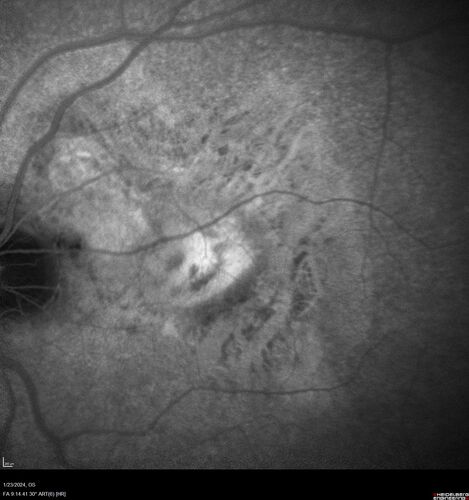

wet AMD with classic extrafoveal macular neovascularization in the good eye

89 year old man with longstanding vision loss in the left eye presented with one month of mild vision loss in the right eye.  Vision was 20/32.  This eye responded to vabysmo therapy.